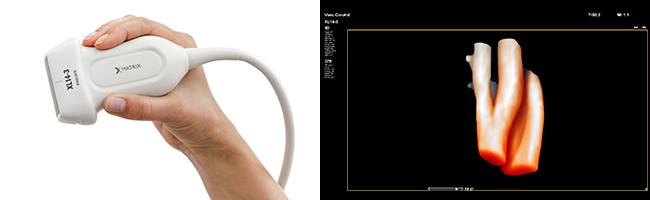

nSIGHTイメージングとPureWaveクリスタル技術の併用で,描出困難だった患者において,より検査に適した画像の描出が期待でき,Live 3Dエコーでは,高解像度でリアルタイム性の高い画像が期待できます。

成人用Live3Dエコー

経食道用Live3Dエコー

腹部用Live3Dエコー

小児用Live3Dエコー

血管・甲状腺用Live3Dエコー